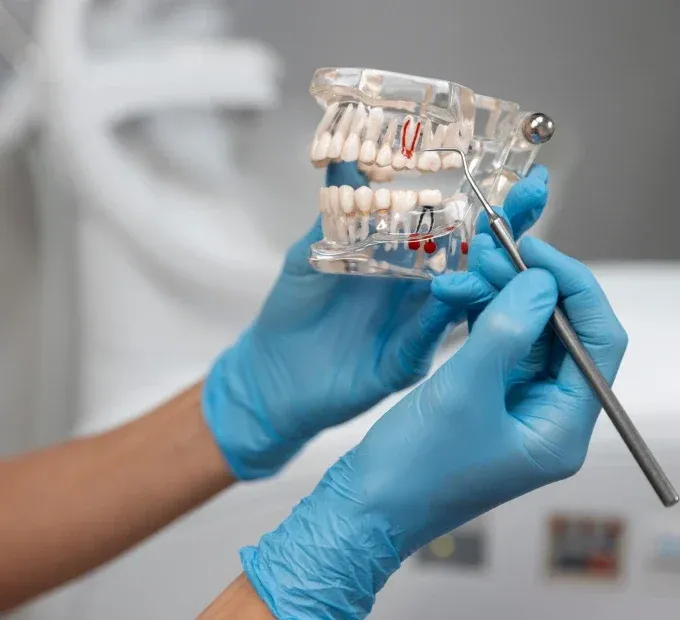

Welcome to our state-of-the-art dental clinic, where we prioritize your oral health with expert care, advanced technology, and a patient-first approach.

Whether you need routine check-ups, cosmetic enhancements, or specialized treatments, we are here to help you achieve a healthy and radiant smile.

General Dentistry

Orthodontics

Pediatric Dentistry

Oral Surgery

Endodontics

Cosmetic Dentistry